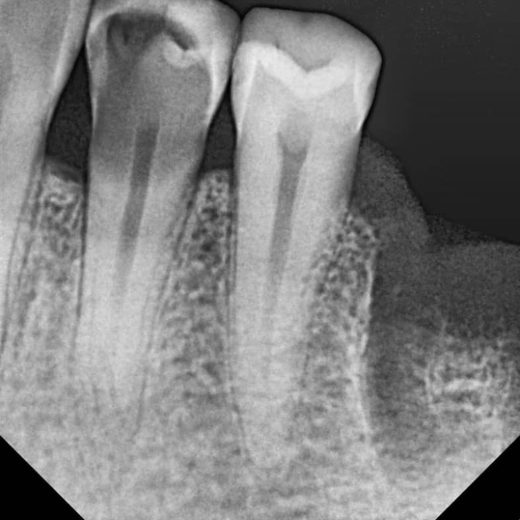

پرمولر سه کانال پایین

3 Canal Lower Premolar